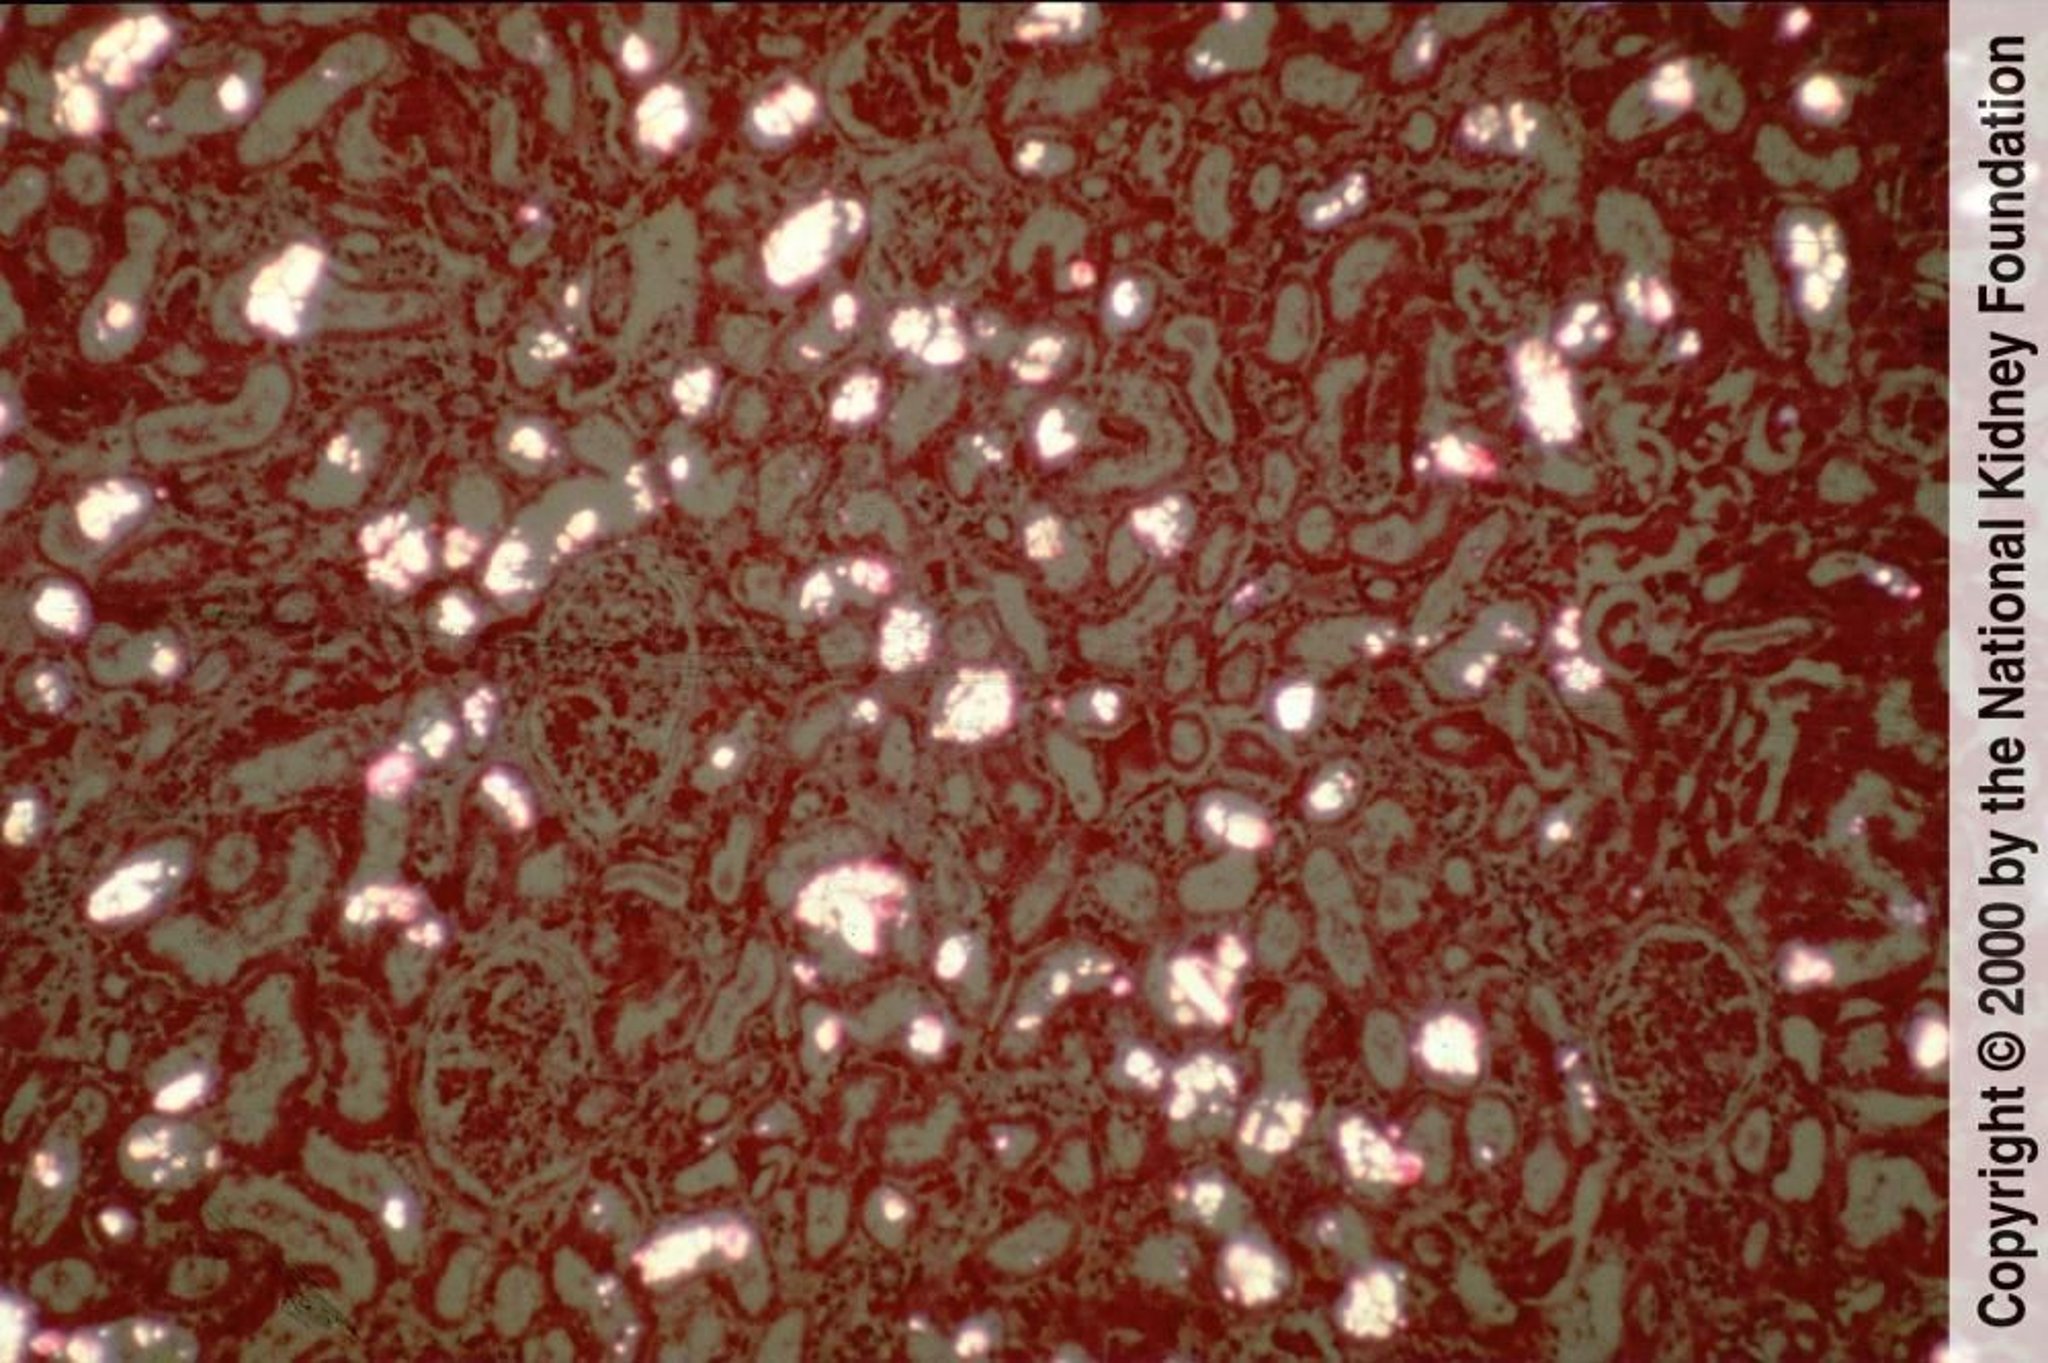

Die Biopsieprobe zeigt Mikrotophi, die aus nadelförmigen Kristallen innerhalb des Tubulus bestehen, mit tubulärer Degeneration und umgebender Entzündungsreaktion und Fibrose. Die Tophusbildung ist heute selten, und die Biopsiebefunde sind in der Regel unspezifisch und umfassen Arteriolosklerose, interstitielle Fibrose und tubuläre Atrophie (Hämatoxylin-Eosin-Färbung, ×200).

Image provided by Agnes Fogo, MD, and the American Journal of Kidney Diseases' Atlas of Renal Pathology (see www.ajkd.org).